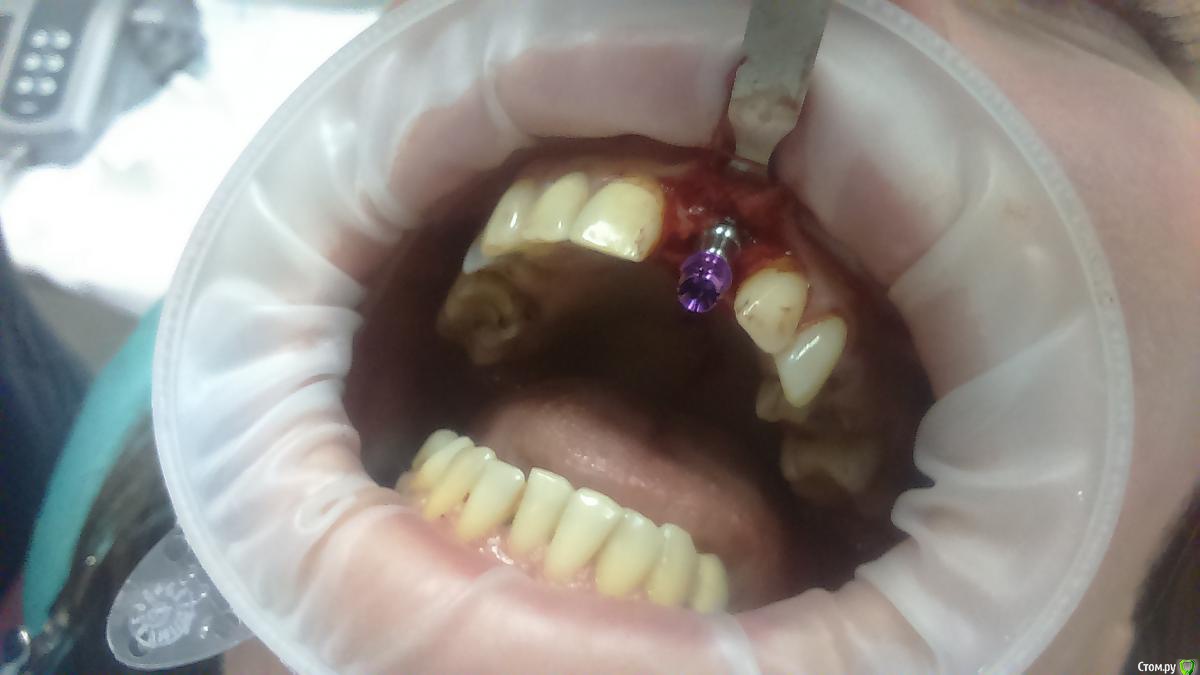

Platon Опубликовано 31 января, 2016 Автор Поделиться Опубликовано 31 января, 2016 Продолжение.не судите строго за фото, первый раз вообще фоткаю операцию)спасибо за советы.По порядку. После того, что мне написали, я решил все -таки уговорить на конусный имплантат (3.7-11.5 ImplantDirect). Также ортопед не хотел делать временную коронку, сказал что сделает каппу, птичку в топку -тоже сделали. Слизистая в области 21 была в рубцах. Исходя из этого всего я решил, коль временной коронки не будет, то сст подсаживать тоже не стану пока,(ортопеда уговаривал сделать временную коронку)))- торк был хороший 35-50н) для того чтобы сст попрактиковаться, но(((.в итоге, анестезия, разрез, сверло пилотное и сверло 2.2, далее расщепление с помощью набора майзенгер с использованием спредеров до нужного диаметра, установил имплантат, торк контролируемый, можно было подобрать любой) в итоге оставил 35. заглушка, совсем немного ксено, мембрана, ушился. ждем. Будет что-то типо каппы которая слегка отдавливает десну,формируя сосочки. не знаю, ни разу такую еще не видел.планирую на этапе раскрытия все-таки сст и временную коронку увидеть.вот. через 4 мес. выложу, что получилось) Если есть советы, критика, всему буду рад, спасибо 3 Ссылка на комментарий